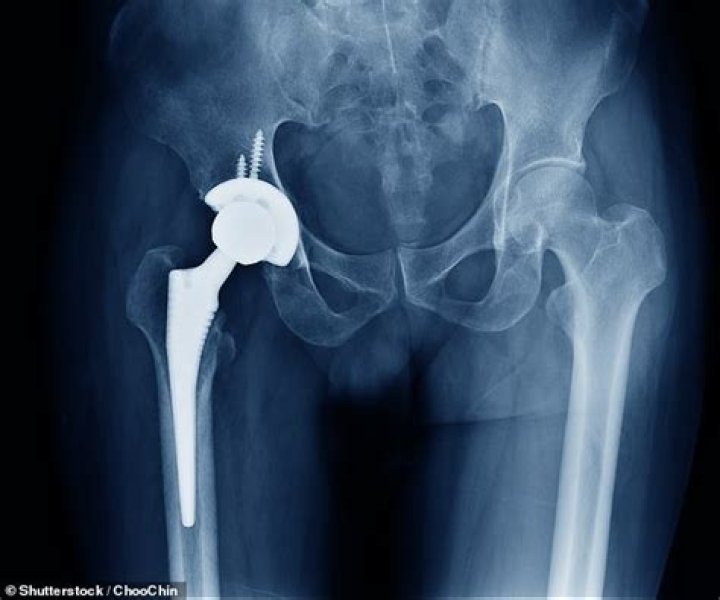

Renee Geyer Death Cause: Hip Surgery Complications Led To Tragic Death

The iconic husky vocal died at the age of 60 due to complications of hip surgery. Her family confirmed the news on Tuesday afternoon.

Since then, the question behind her death has been a top topic of discussion, she was at the hospital for hip surgery, and that went wrong.

Along with complications of the surgery in the hospital,  it was discovered that Geyer had inoperable lung Cancer, which might threaten her hip surgery.

Geyer’s family said, “It is with immense sadness that we announce that Renée Geyer has passed away from complications following hip surgery.

It was discovered that Renée also had inoperable lung Cancer. She was in no pain and died peacefully among family and friends. Naturally, we are all utterly devastated,”